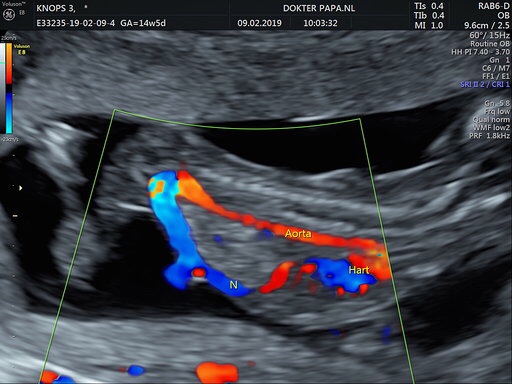

About Annette de Graaf: - Born on 17 augustus 1983 - Loves to learn about learning - Spreads kindness like confetti - Never stopped playing - Nature admirer - Big believer of 'it's the little things that matter the most' - Wife of Thaddeus Knops - Mother of Jools (2013), Pippa (2015) & Sol (2019) - Proud founder of Flow School Norway - Author of 'Let's Grow: Raising Children with a Growth Mindset' - Designer of My Learning Story & Flow Learning - Travel Blogger (The Flying Dutch Family & KLM) - Norway Lover - Mindset Coach (for families & schools) - Connection, Engagement & Flow Workshop Leader (for schools) Bekijk alle berichten van Annette de Graaf